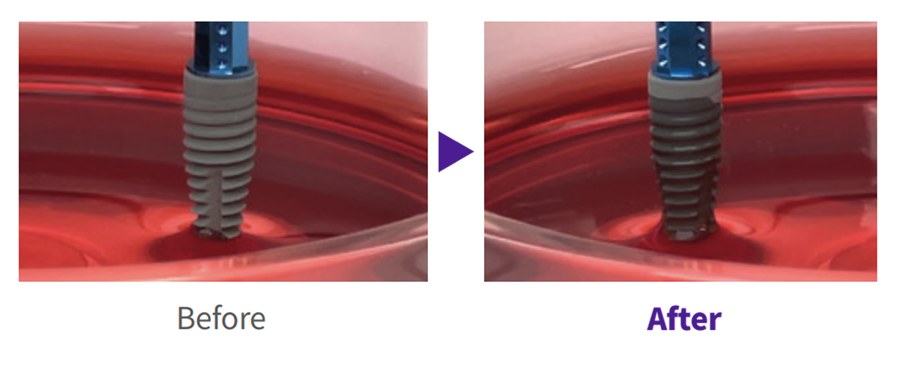

Plasma Surface Treatment Matters

During manufacturing, shipping, and long-term storage,

hydrocarbons can build up on the implant surface over time,

which may reduce biocompatibility.

Plasma implants use high-energy plasma

to remove hydrocarbons

and reactivate the surface for higher biocompatibility.

During manufacturing, shipping, and long-term storage, hydrocarbons can accumulate on the implant surface, reducing biocompatibility. Plasma implants remove hydrocarbons with high-energy plasma and reactivate the surface for higher biocompatibility.

Creating a safer implant surface through removal of surface impurities

Improved early protein attachment through organic removal and surface activation